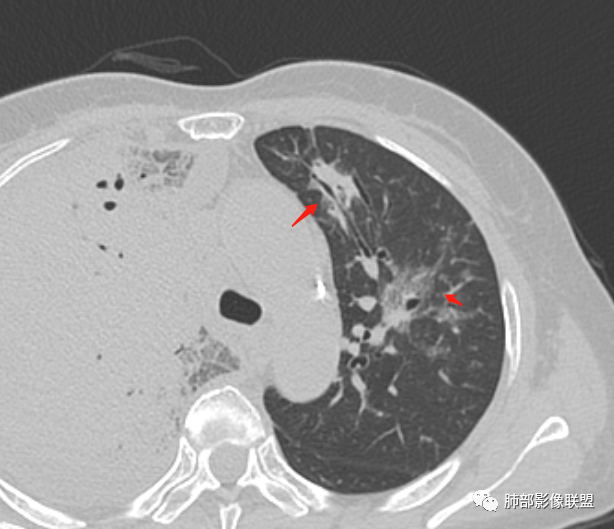

第一次CT:

首先考虑感染性病变,合并右侧胸腔积液,增强扫描强化明显,左侧也有少许感染,病变无坏死,可见支气管充气征,支气管镜上叶管腔狭窄,未见新生物。

右肺大叶实变,支气管扩张,有强化,胸腔积液考虑淋巴瘤 ,鉴别奴z卡,结核感染。

急性起病与影像表现不符,右肺大片状实变,内见支气管通气象,部分支气管不规则扭曲。左肺磨玻璃病变增多。考虑腺癌可能。

右肺肿块,极度不规则,内部有空气支气管,增强扫描中度不均匀强化。左肺有多发片状实变,边界清,内部有支气管穿行。左侧大亮胸腔积液。胸闷,咳白痰。支持恶性肿瘤,腺癌可能

起病急,发热,腹部不适,血象,PCT明显升高,右肺实变,支气管走形可,强化均匀,胸腔积液,短期内左肺病变进展明显,考虑感染,军团菌?

右肺实变,密度支气管呈枯树枝样,增强扫描中度不均匀强化。左肺有多发片状实变,边界清晰,内部有支气管穿行。右侧胸腔积液。考虑恶性,腺癌,鉴别淋巴瘤。

右肺大片实变,内支气管充气呈枯树枝样,上叶支气管狭窄,右侧大量胸腔积液,左肺可见多发斑片影,边缘模糊,铁蛋白明显升高,考虑腺癌?粘液腺癌?鉴别鹦鹉热

右肺实变,胸腔积液,支气管充气征,血管造影征,左肺斑片状高密度,支气管血管束走行,边缘模糊,累及间质,一元,感染,鹦鹉,鉴别粘液腺癌。

两肺斑片影,右侧中大量胸水,复查减少,右侧气管征,临床也没有大量泡沫痰,气管镜没有找到肿瘤证据,还是考虑感染性病变,似乎有结节感,结核?军团,鹦鹉?其它如努卡,绿脓杆菌需要基础病支持,暂不考虑,粘液腺癌鉴别

老年女性。右肺实变,支气管枯树枝征,增强中度不均匀强化,胸腔积液。左肺有多发片状絮状影,边界不清,内部有支气管穿行。病史受凉后咳嗽咳痰,实验室炎性指标升高。考虑感染性病变,鹦鹉热,军团,鉴别粘液腺癌,淋巴瘤。

定肺部感染疾病:主体病灶位于右肺上叶大范围实边,结构密实,实边内支气管充气征,周围间质受累,余肺叶散在气道分布小片实边影,边缘模糊,右侧胸腔大量积液,起初发病WBC,PCt和血沉高,革兰氏阴性杆菌肺炎(肺克雷伯杆菌肺炎?)与急性纤维素性肺炎鉴别,必要时支气管镜肺泡灌洗液NGS检查!

女,65,胸闷、气短6天。胸部CT:左肺多发斑片实变影/GGO,边缘模糊,隐约有小叶内间隔增厚,沿支气管束分布。右上叶大叶性实变影,支气管充气征,部分管腔扩张;右中下叶大片实变影,沿支气管分布,边缘清晰、内收明显。右侧胸腔积液,纵隔可见肿大淋巴结。考虑:TB?PC?鉴别粘液腺癌。